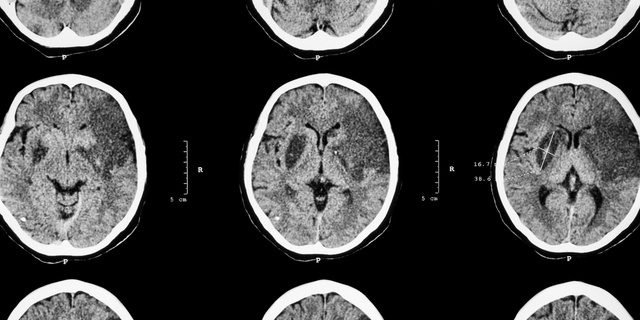

・頭部CT検査

また、アルコールの脳への影響による意識レベル低下や、運動失調により転倒し頭部外傷や骨折を呈していることがあります。

頭部外傷は転倒時の切り傷やタンコブ(頭血腫)程度ならばよいのですが、外傷性頭蓋内出血や頭蓋骨骨折を生じていることもあるのです。

他にもアルコールの作用による脱水や血圧低下による 脳梗塞、 糖尿病を背景とした重度の 低血糖や高血糖、高アンモニア血症など肝障害の悪化についてもチェックします。